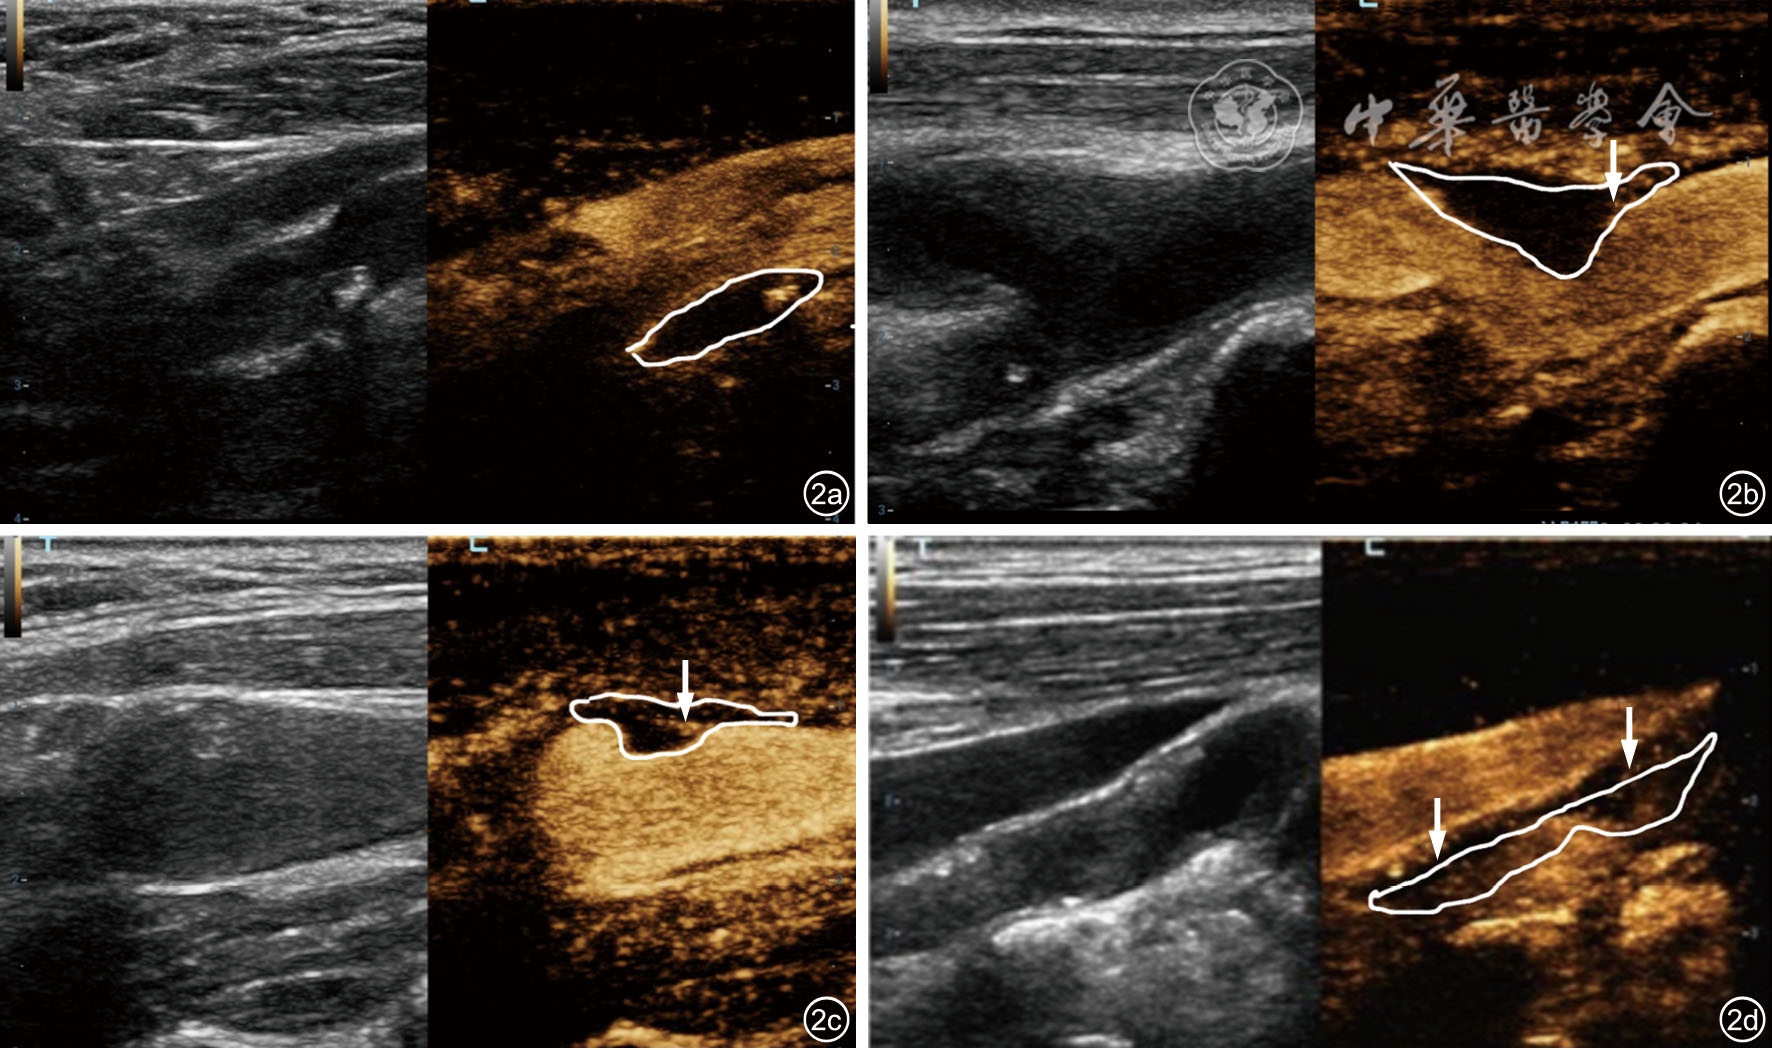

图2 颈动脉斑块内不同新生血管(IPN)分级的超声造影(CEUS)表现。图a为IPN 0级(左图为常规超声,右图为CEUS):未见明显增强灶(白色轮廓内未显示造影剂微气泡灌注),提示无新生血管形成;图b为IPN 1级(左图为常规超声,右图为CEUS):见斑块上肩部见造影剂微气泡灌注,呈点状增强(白色箭头所示),提示少量新生血管形成,分布局限;图c为IPN 2级(左图为常规超声,右图为CEUS):斑块内见数个造影剂微泡灌注(白色箭头所示),增强范围有限,未累及整个斑块;图d为IPN 3级(左图为常规超声,右图为CEUS):斑块内可见多个造影剂微泡,呈线状和片状增强(白色箭头所示),造影剂广泛分布于斑块实质,提示丰富的新生血管形成